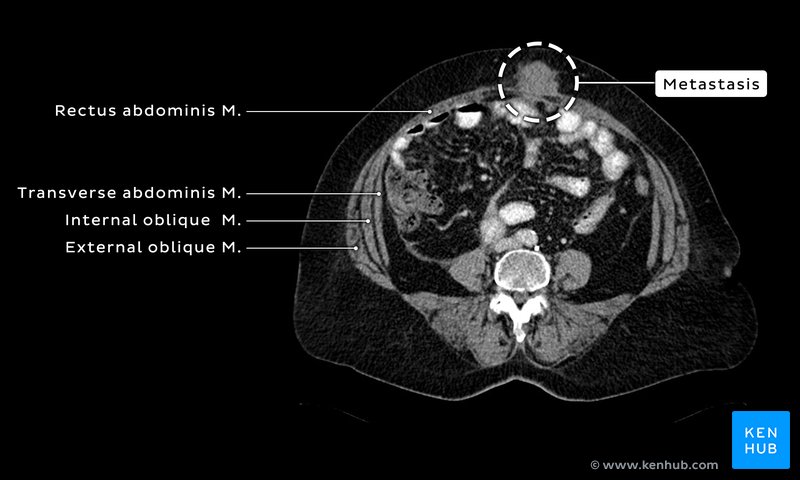

Imaging by CT and MRI confirmed the presence of the mass and revealed intra-abdominal and right lung metastatic lesions (Figures 2-4).

The function of the omentum (greater) is not clear. But, regardless, it does contact virtually all abdominal and some pelvic organs (Figure 8). The omentum may act as a bandage in cases of infection or intestinal rupture because it can drape and attach itself to areas of inflammation. The omentum can play a role in the spread of cancer, especially ovarian, colon, and gastric cancers. Because the omentum is rich in blood vessel, cancer cells that have separated from the primary cancer can implant and grow in the omentum, i.e., omental metastasis. It is likely the omentum did play a role in the spread of cancer in this case. Omental cake is the term that refers to infiltration of the omental fat by material of soft-tissue density (e.g., cancer cells). The name refers to the contiguous omental mass, which in some ways resembles the top of a cake. It is readily seen radiologically and referred to as omental caking (Figure 9).